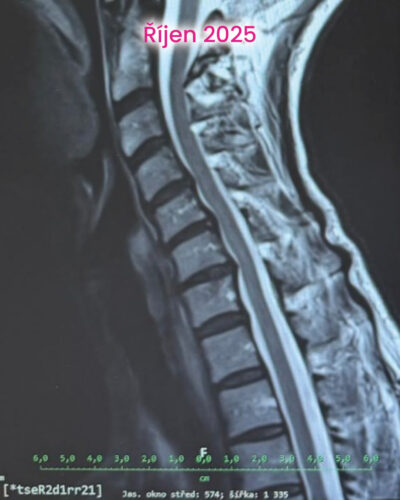

První změny přišly překvapivě rychle. Bolest začala ustupovat, brnění se objevovalo méně a spánek se postupně vracel. Přidaly jsme nordic walking pod vedením instruktora. V září byla klientka bez bolesti, spala bez přerušení a fungovala normálně v pohybu i běžném životě. V prosinci už si zase mohla nazout skialpové bot, skialpy a vyrazit na krátký trek.

To, co bylo cítit subjektivně, potvrzovala i data. Na začátku byla na 49 %. Postupně se dostala až na 87 % a dnes se stabilně drží kolem 79 %. To není „náhodné zlepšení“. To je stabilizovaný stav.

Zelené zóny převažují a zatížení je rozložené mnohem rovnoměrněji. Reflexní mapa ukazuje klidnější nervový systém. A svaly už nefungují v režimu neustálé kompenzace. To zásadní ale není na obrázcích. Největší změna je v tom, že tělo přestalo bojovat samo proti sobě.